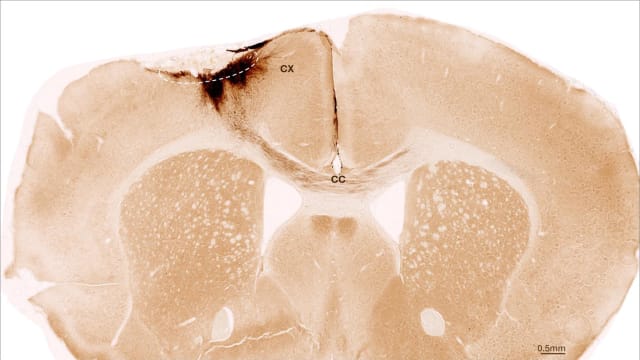

Das Bild zeigt einen koronalen Schnitt durch das Gehirn einer Maus nach einem Schlaganfall und der Transplantation neuronaler Stammzellen. Die gestrichelte Linie markiert den Bereich des Schlaganfalls. Die Axone der transplantierten Zellen sind dunkelbraun gefärbt. Sie erstrecken sich lokal in den Kortex (CX), aber auch über den Balken (Corpus callosum, CC) in die gegenüberliegende Gehirnhälfte | Bild: UZH

Eine Woche nach dem Schlaganfall transplantierte das Team neuronale Stammzellen in die betroffenen Hirnregionen und beobachtete die Entwicklung mit einer Vielzahl an bildgebenden und biochemischen Methoden. «Es zeigte sich, dass die Stammzellen den gesamten Analysezeitraum von fünf Wochen überlebten und sich grösstenteils zu Nervenzellen umbildeten − die sogar mit den bereits vorhandenen Hirnzellen kommunizierten», sagt Tackenberg.